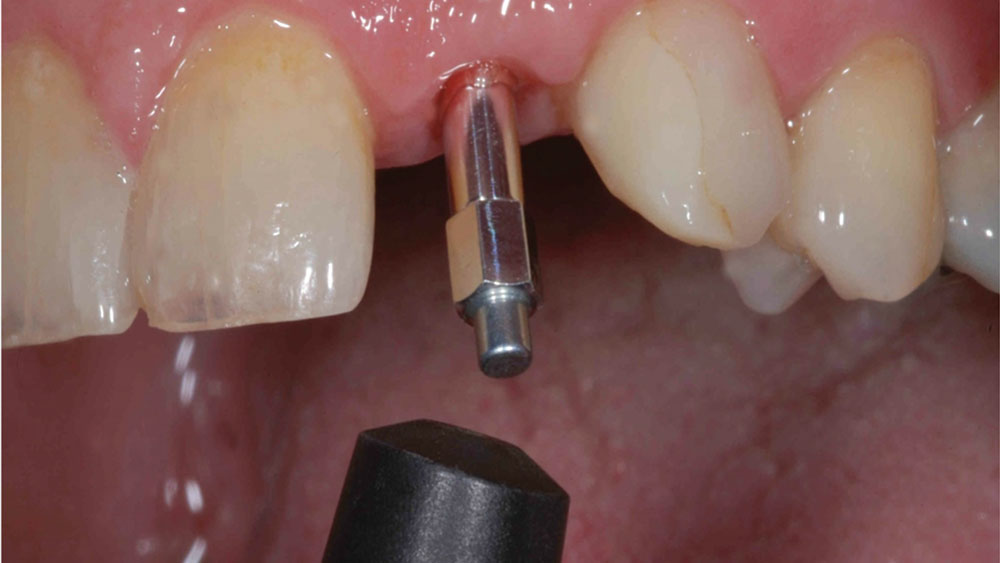

To achieve an optimal functional and esthetic outcome, the implant must be placed correctly with regard to trajectory, adjacent vital anatomy, and buccolingual, apicocoronal and mesial-distal positioning. Situating the implant so that the edges of the osteotomy are at least 2 mm from the buccal and lingual cortical plates, 2 mm from adjacent roots, 2 mm from vital structures, and 2–3 mm below the crest of tissue will keep the implant within the envelope of acceptability. The implant trajectory should emerge lingual to the incisal edge of the planned restoration, which allows for a screw-retained crown.

This case is an example of an ideal clinical situation for dentists who are new to placing implants in the esthetic zone. The patient requested treatment for a fractured upper lateral incisor. After extraction, grafting and healing, ample bone and soft tissue were present, and an implant was placed in optimal position for an esthetic result. The screw-retained restoration predictably restored form and function, illustrating the beautiful results that can be achieved by observing simple surgical and prosthetic guidelines.